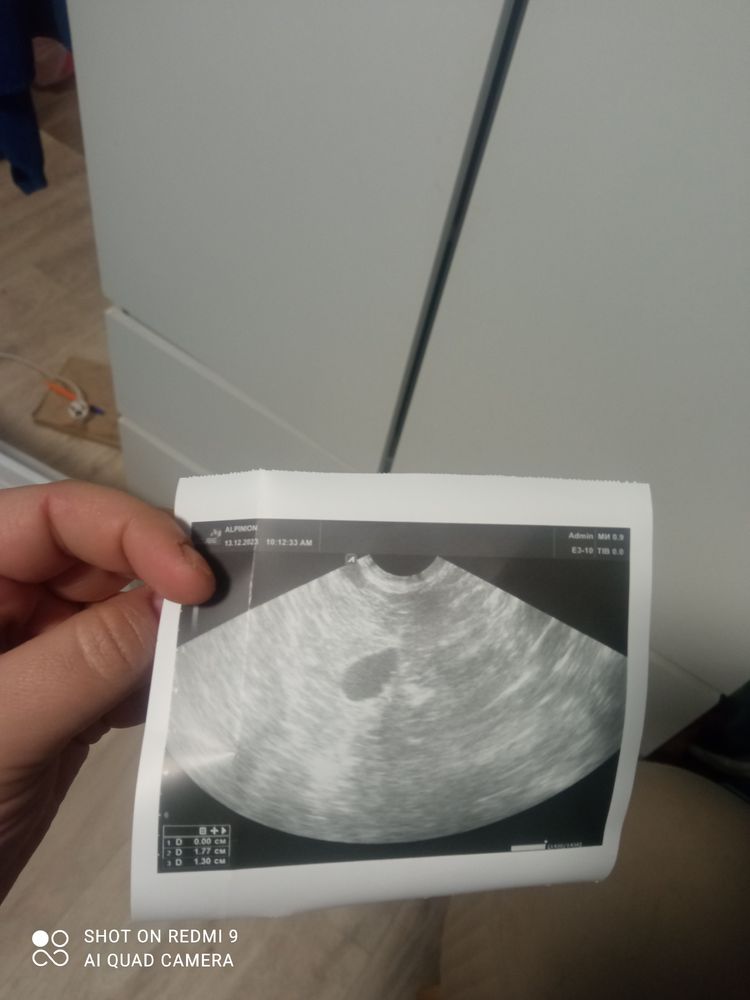

Месячных нет, гинеколог сказал это жидкость . Когда сдавала кровь на ХГЧ 0.2 Прошло после УЗИ 5 дн

Диана → Зачатие Анализы Мама мальчика (5 лет), планирую беременность Москва Что это подскажите Месячных нет, гинеколог сказал это жидкость . Когда сдавала кровь на ХГЧ 0.2 Прошло после УЗИ 5 дн Посмотрите еще 20 записей на эту тему Прогестерон и овуляция 10 дпо, результат анализа на хгч Похожие записи ПОДСКАЖИТЕ Подскажите как быть. Подскажите подскажите подскажите.... Чаты Беременных Выберите чат: Июлята-2026 Августята-2026 Сентябрята-2026 Октябрята-2026 Ноябрята-2026 Декабрята-2026